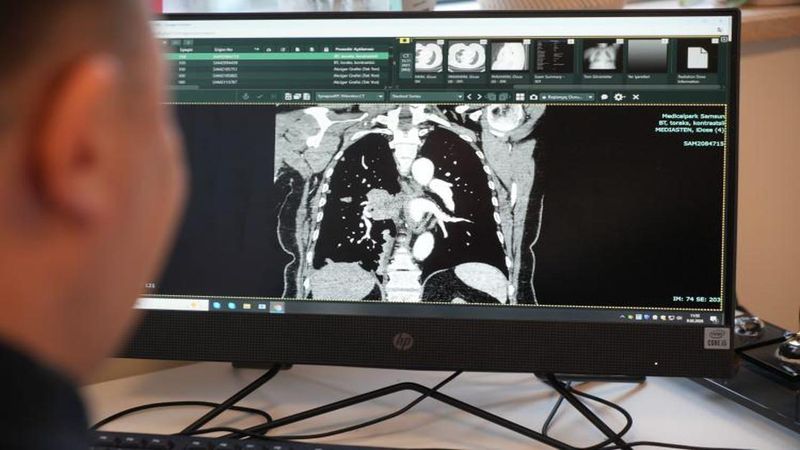

Göğüs Hastalıkları Uzmanı Prof. Dr. Şevket Özkaya, kanserin biyolojik yaşlanma süreciyle bağlantılı olduğunu belirtti. Özkaya, "Bugün bildiğimiz üzere yaşayan her hücrenin sonu kanserdir. Sadece hangi organ ve ne zaman ortaya çıkacağını henüz bilemiyoruz" dedi.

Kanser türlerine de değinen Özkaya, akciğer kanserinin büyük oranda sigara ve hava kirliliğiyle ilişkili olduğunu, mide kanserinin çoğunlukla Helicobacter pylori enfeksiyonuna bağlı olduğunu söyledi. Rahim ağzı (serviks) kanserinin ise neredeyse tamamen insan papilloma virüsünden (HPV) kaynaklandığını belirtti. Bu durumun aşılama ve enfeksiyon kontrolünün önemini gösterdiğini vurguladı.